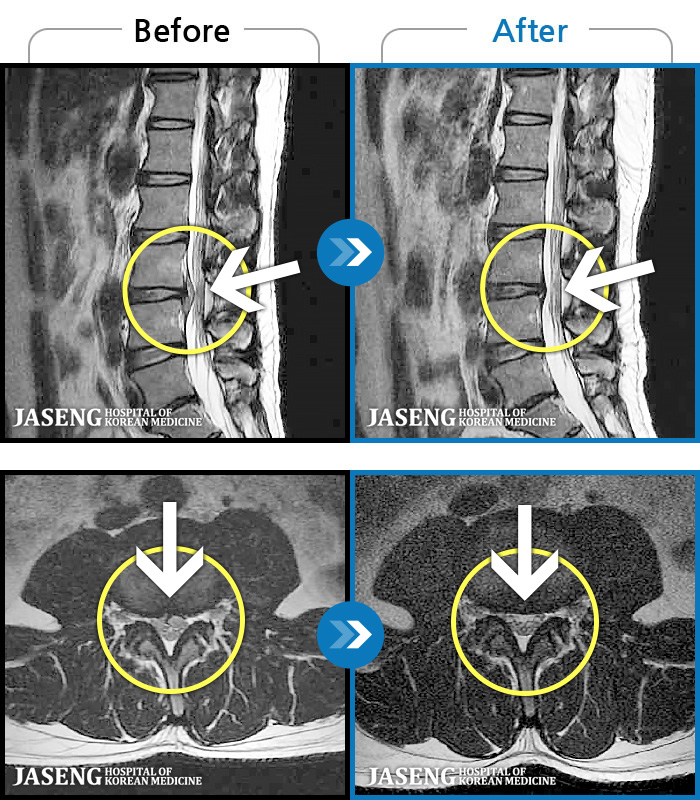

123 MRI ũ ʸ Ȯϼ.